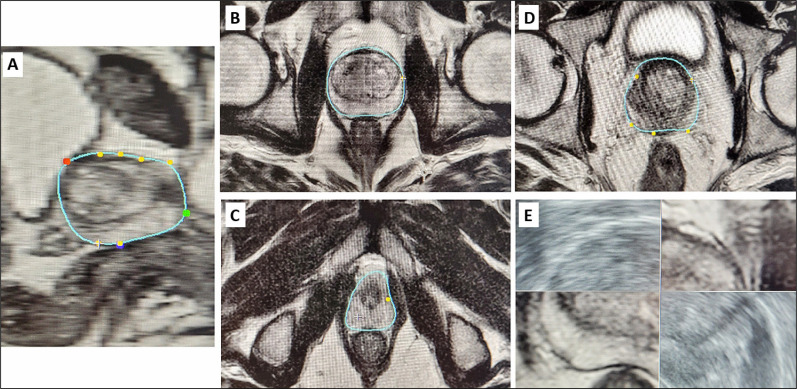

Introduction: The incidence of prostate cancer is increasing in Poland, particularly due to the aging population. This review explores the potential of deep learning algorithms to accelerate prostate contouring during fusion biopsies, a time-consuming but crucial process for the precise diagnosis and appropriate therapeutic decision-making in prostate cancer. Implementing convolutional neural networks (CNNs) can significantly improve segmentation accuracy in multiparametric magnetic resonance imaging (mpMRI).

Results: The results indicate that CNNs, particularly those utilizing the U-Net architecture, are predominantly selected for advanced medical image analysis. All the reviewed algorithms achieved a Dice similarity coefficient (DSC) above 74%, indicating high precision and effectiveness in automatic prostate segmentation. However, there was significant heterogeneity in the methods used to evaluate segmentation outcomes across different studies.